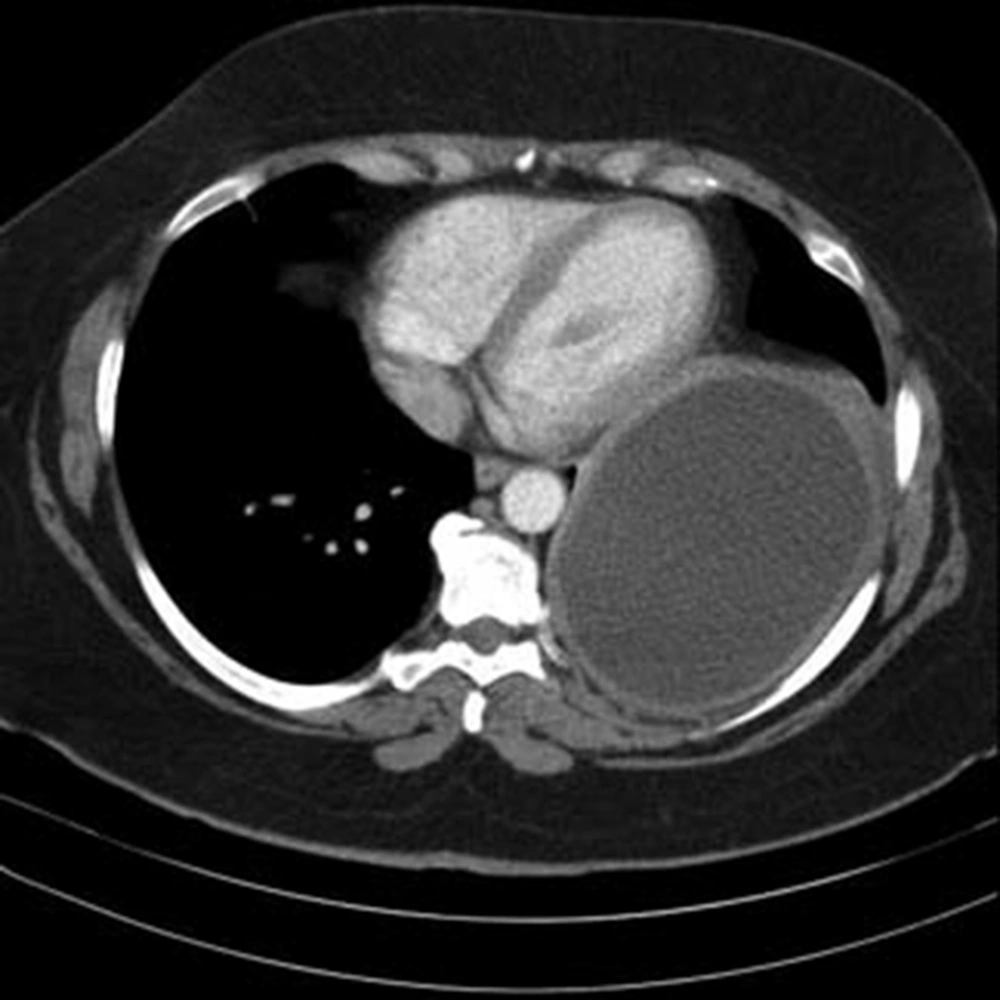

The patient was a 42 year old woman with pulmonary hydatid cyst who was admitted for left thoracotomy. She weighed about 110 kg and her body mass index (BMI) was about 42 kg/m2. She had a history of asthma since two years ago which was under treatment by inhaled Salbutamol and Seretide (PRN). In chest CT scan a large thick walled homogenous cystic lesion (12 cm, 5.8 cm, 8 cm) was seen in the left lower hemi-thorax (Figures 1 and 2).

In trans-thoracic echocardiography, cardiac ejection fraction (EF) was reported about 55% with normal left and right ventricular size and function; however, a large cystic mass in postrolateral of pericardium was also noted. The chest radiography revealed a mass lesion with a homogenous shadow in the left lung (Figure 3).